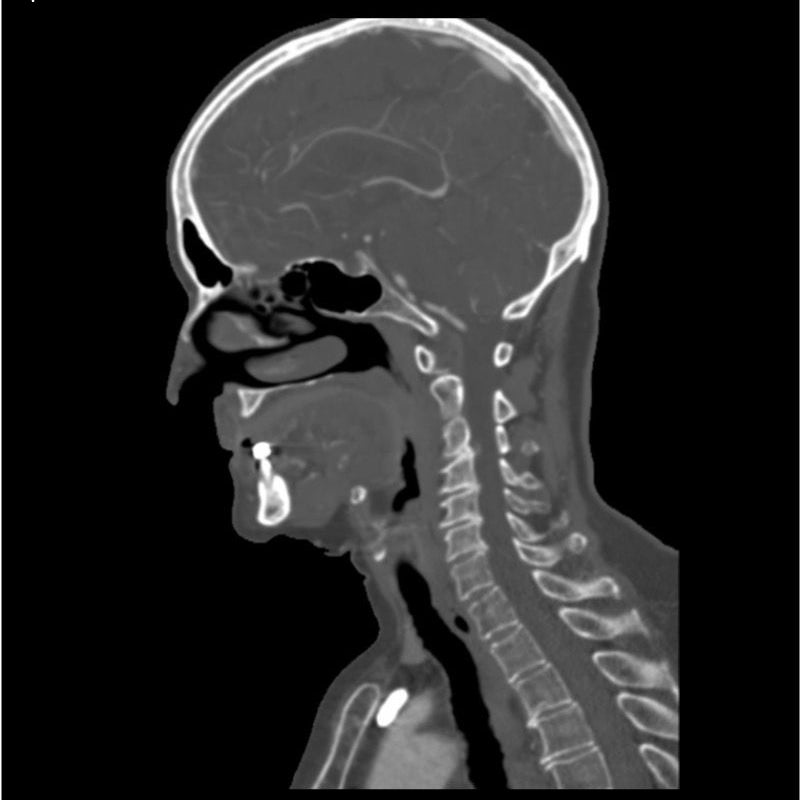

This phantom simulates a contrast medium enhanced head in arterial phase (CT angiography). The neck and upper thorax are included up to the aortic arch and the fifth thoracic vertebra. The vertex is included until approximately 0.5 cm below skin level. The thoracic phantom section excludes shoulder and back parts that are typically not part of CTA examinations. The interncal carotid artery has calcifications on both sides with moderate stenosis on the right side. Otherwise, the phantom has no significant vascular pathologies.

The phantom can be used in CT (including CBCT) to evaluate and optimize CTA imaging performance and post-processing applications such as vessel segmentation, including AI-enabled applications. It is also nicely suited for training purposes. The phantom provides a detailed and realistic simulation of vascular structures, soft and bone tissue, including small details such as lymph nodes. Air voids are filled with a cellulose-polymer composite of approx. -160 HU.

Realistic simulation of head and neck vessels up to the aortic arch, bone and soft tissues.

Calcifications of the internal carotid artery at the carotid bifurcation on both sides with mild stenosis on the right side.